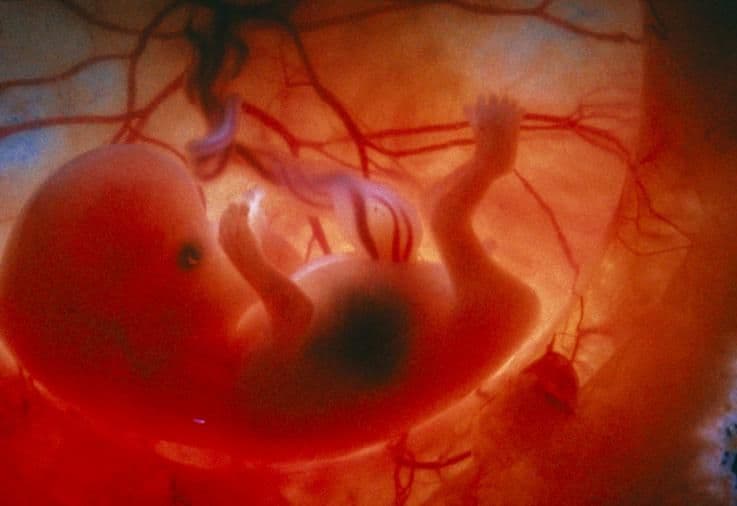

The umbilical cord gradually becomes more coiled as the pregnancy progresses – as seen here on the left of the image. This coiling is thought to occur because of the many movements the baby makes.

Your baby takes on a more human form as his neck lengthens and his head is seen as separate from his body. The head is still about half the total length of your baby. The length of your baby can be measured on an ultrasound by measuring the distance between your baby’s head (crown) and his bottom (rump). This is noted as the CRL (crown-rump length) measurement. The head is also measured: this is the biparietal diameter (BPD), which is the distance between the two parietal bones on each side of the baby’s head.

Now that the neck is more developed and all the limb joints have formed, your baby can begin to make several movements. The completed diaphragm allows for breathing movements. In the gut, your baby’s duodenum now opens up along its length, the small bowel starts to rotate and prepares to re-enter the abdominal cavity.